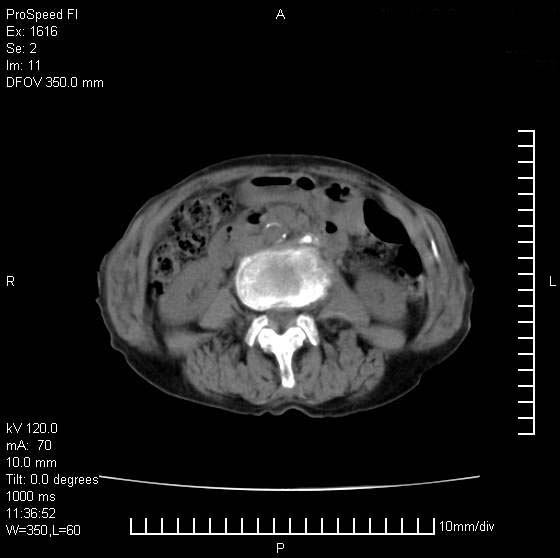

患者无明显临床症状,肝左叶发现一个圆形密度不均的低密度灶,边界较清楚,大小37x45mm,ct值35-70,患者犹豫做增强,如有增强片,我再发上,现先请各位老师会诊.

左肝外叶可见较大圆形低密度影,病灶可见较光整清晰边界,病灶内可见多量条状稍高密度影,右肝前叶亦可见圆形结节状低密度影,边界清晰,密度均匀,考虑1肝多发囊肿,左肝囊肿内出血2肝包虫病3左巨块型肝癌出血合并右肝转移或合并右肝囊肿

左肝外叶可见较大圆形低密度影,病灶可见较光整清晰边界,病灶内可见多量条状稍高密度影

考虑:肝包虫病

肝左叶类圆形低密度影,内可见略高密度影,边界清晰周边可见环形低密度带,考虑肝腺瘤可能,建议增强扫描除外肝血管瘤与肝癌

肝左叶不均匀占位,内有斑片状高密度出血灶,内侧缘似有假包膜,腹主动脉周围及肝门区结构紊乱,似有增大淋巴结,考虑:肝左叶hcc并淋巴结转移。建议增强扫描除外其他。